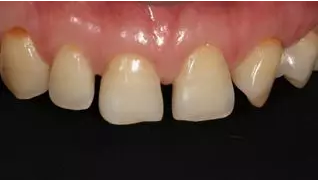

術后上前牙正面照

病例分享|復合樹脂微創(chuàng)美學修復關閉上前牙間隙